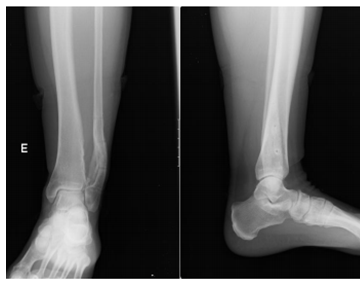

The authors present the case of a female patient, 45 years old, with neoformation in the left tibia, with several years of evolution. It was a massive osteochondroma of the distal tibia involving the left tibio-peroneal syndesmosis (Figure 1) and fibula deformity. The patient observed apparent increase in size in recent years with episodes of associated pain or discomfort in this location.

Figure 1 Left ankle X-Ray that demonstrates exostosis in the distal tibia, causing pressure and deformity in the fibula.